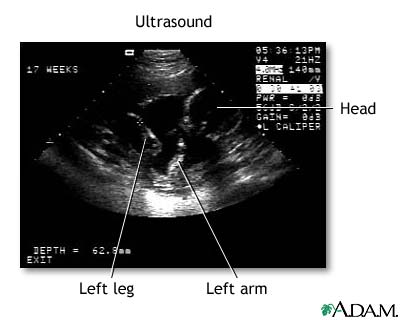

Ultrasound - series: Procedure, part 3

Don't get your hopes up too much about this first, fleeting look at your baby. The black-and-white image you see on the computer screen is grainy, shadowy, and may look more like a test pattern than a baby-to-be. Your sonographer will walk you through what you're seeing by pointing out the fetus' developing heart, limbs, and head.